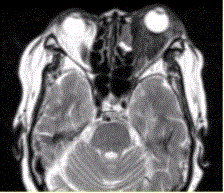

问题 患者女,64岁,左眼突出5年余。查体左眼球前突6mm,眼球运动自如,眼底无异常,下睑扪及边界不清、质软的肿块,视力正常,MR表现如下图。 关于炎性假瘤与眼型Grave病的区别,正确的表述是

选项 A.可发生于甲状腺功能正常者 B.只发生于甲状腺功能正常者 C.突眼程度可与临床表现、实验室检查结果不相符 D.后者为无痛性突眼 E.后者病理改变为眼外肌水肿 F.前者肌腱、肌腹同时增粗,后者肌腹增粗

答案 ACDEF